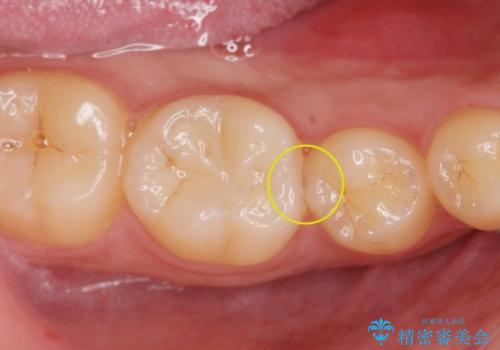

歯と歯の間に虫歯(コンタクトカリエス)がありましたので、拡大鏡下で虫歯を取り、白い詰め物(e-maxインレー)で治療を行いました。

適合の良い詰め物が入りました。